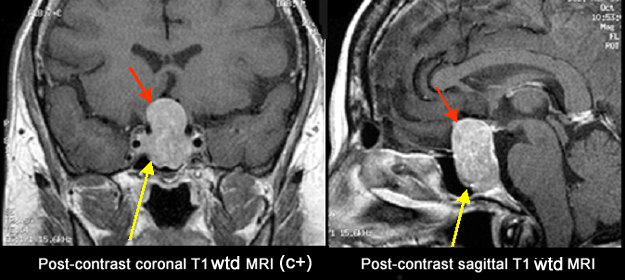

Pituitary Adenoma

Findings: A homogeneously enhancing tumor is seen within the sella (yellow arrow ) with suprasellar extension (red arrow) producing optic chiasm compression.

Microadenomas tend to be small in size and are recognized early due to the hormone secreting features. |